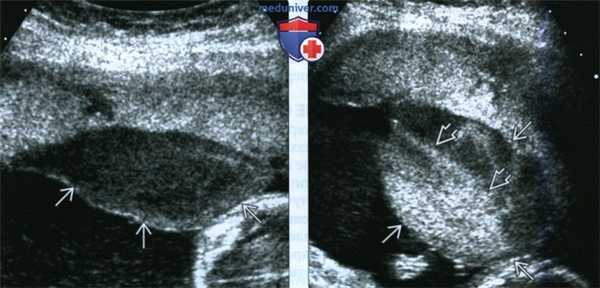

(Слева) УЗИ в поперечной плоскости. Определяется единичное ретрохориальное РМВП крупных размеров. Во время исследования отмечается медленный турбулентный кровоток. РМВП, напоминающее объемное образование, выбухает в амнион.

(Справа) Тот же случай. РМВП спустя некоторое время и после перемены положения матери. Определяется динамика изменения размеров образования. Размеры РМВП увеличились, отмечается уровень осадка в жидкости. Ультразвуковая картина РМВП обусловлена оседанием эритроцитов материнской крови в плазме.

(Слева) Беременность, осложненная ЗРП во II триместре и маловодием. В плаценте определяются несколько эхонегативных образований некоторых из них определяется кровоток.

(Справа) Другой случай. МРТ„ Т2-ВИ. Маловодие и ЗРП. В толще плаценты отмечаются многочисленные гиперинтенсивные очаги При гистологическом исследовании плаценты установлен тромбоз 70% сосудистого русла плаценты, связанный с коагулопатией у матери. Плод погиб внутриутробно.